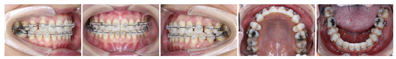

2).上颌粘接0.022英寸(1英寸=2.54 cm)陶瓷自锁直丝弓矫治器(Clippy,TOMY,Japan),16、26粘接直丝弓颊面管。初始弓丝为0.014英寸,依次应用0.016英寸、0.016英寸×0.022英寸、0.018英寸×0.025英寸镍钛方丝初步排齐整平上下牙列。

3).第3个月牙周科行36、46区域骨增量手术:术区翻全厚瓣后,颊侧种植机球钻打孔穿透骨皮质、按照骨增量方向打入钛钉1.5 mm×10 mm(中邦,西安,中国),植入人工骨粉(Bio-Oss,Geistlich,瑞士),高度平齐牙槽嵴顶或高于0.5 mm,宽度与第二磨牙颊舌向宽度基本一致,之后覆盖生物膜(Bio-Guide,Geistlich,瑞士),骨膜松弛切口,龈瓣冠向复位,严密缝合。术后6周开始粘下颌托槽及37、47颊面管,初始弓丝为0.014英寸。第9个月更换至上颌0.018英寸×0.025英寸、下颌0.017英寸×0.025英寸不锈钢方丝,滑动法内收前牙、近中移动并直立37、47。治疗过程中37、38出现舌倾,配合局部方丝弓正转矩控制(图2)。

4).第13个月下颌缺牙间隙基本关闭,逐步粘结38、48带环进一步排齐关闭剩余间隙。第25个月下颌更换0.018英寸×0.025英寸不锈钢方丝进一步直立第二三磨牙(图3)。

像矫治结束后面像显示患者侧貌改善明显,鼻唇角恢复正常,颏部形态有所改善。口内像显示上下前牙覆

覆盖正常,中线对齐,双侧尖牙中性关系、磨牙完全远中关系,尖窝交错,缺牙间隙关闭未见明显龈退缩。曲断片37、38、47、48得到直立牙根平行较好,未发现明显的牙根吸收和齿槽嵴骨吸收的情况。临床检查下前牙区有少量龈退缩及牙龈黑三角情况(图5)。保持期追踪显示牙齿咬合排列保持良好拥挤间隙未见复发,缺牙间隙闭合紧密,面型良好(图6)。治疗前后的锥形束CT对比显示,植骨区域牙槽骨宽度有显著增加,移入缺隙内的下颌第二磨牙及第二前磨牙未见骨开窗骨开裂(图7)。